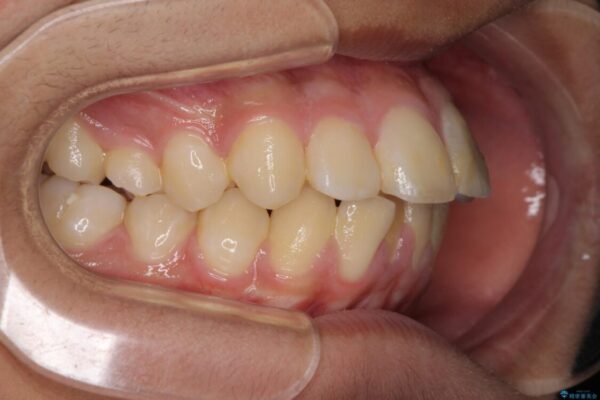

口元の突出感を気にして来院された患者様です。

上下前歯が著しく前突している状態であったので、上下左右の第1小臼歯4本を抜歯し、ワイヤー装置にて矯正治療を行うこととしました。

舌の突出癖により、前突になったと考えられたため、舌のトレーニングをしっかりと行うよう指導しました。

治療前

• 膨らんだ口元 ワイヤー装置での抜歯矯正 治療前画像